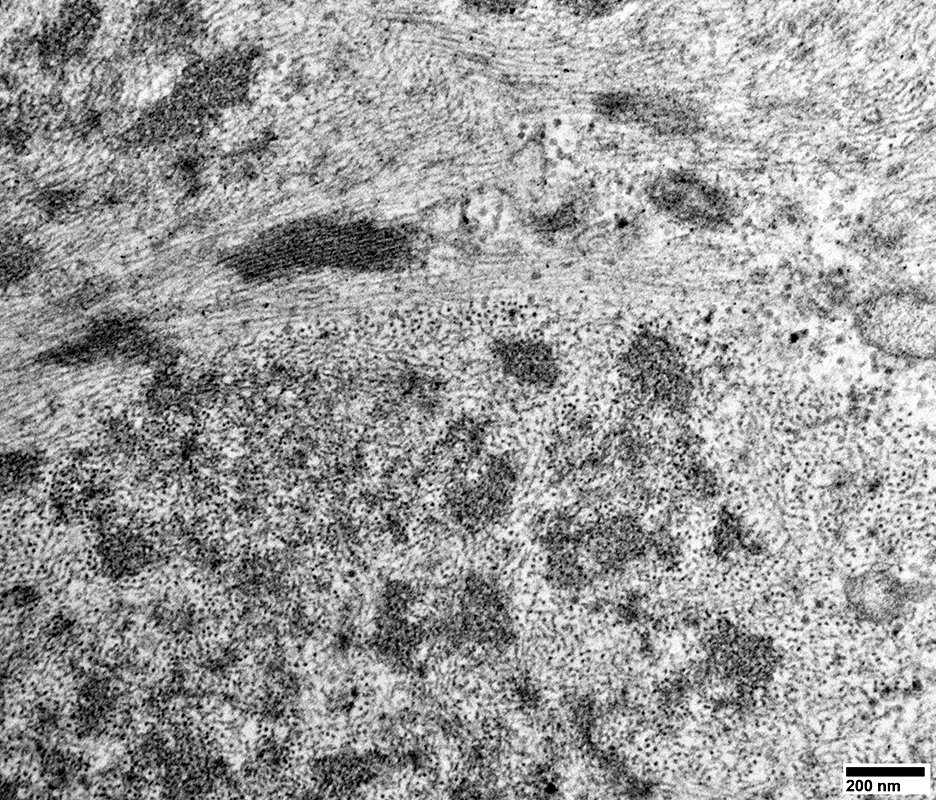

DM-VP: Aggregate Ultrastructure

From: R Schmidt

Muscle fiber cytoplasm contains

Aggregates: Small; Multiple; Scattered

Mitochondria: Mostly small

Few sarcomeres

Aggregates in muscle fiber cytoplasm (Arrow)

Shape: Irregular

internal architecture: Punctate